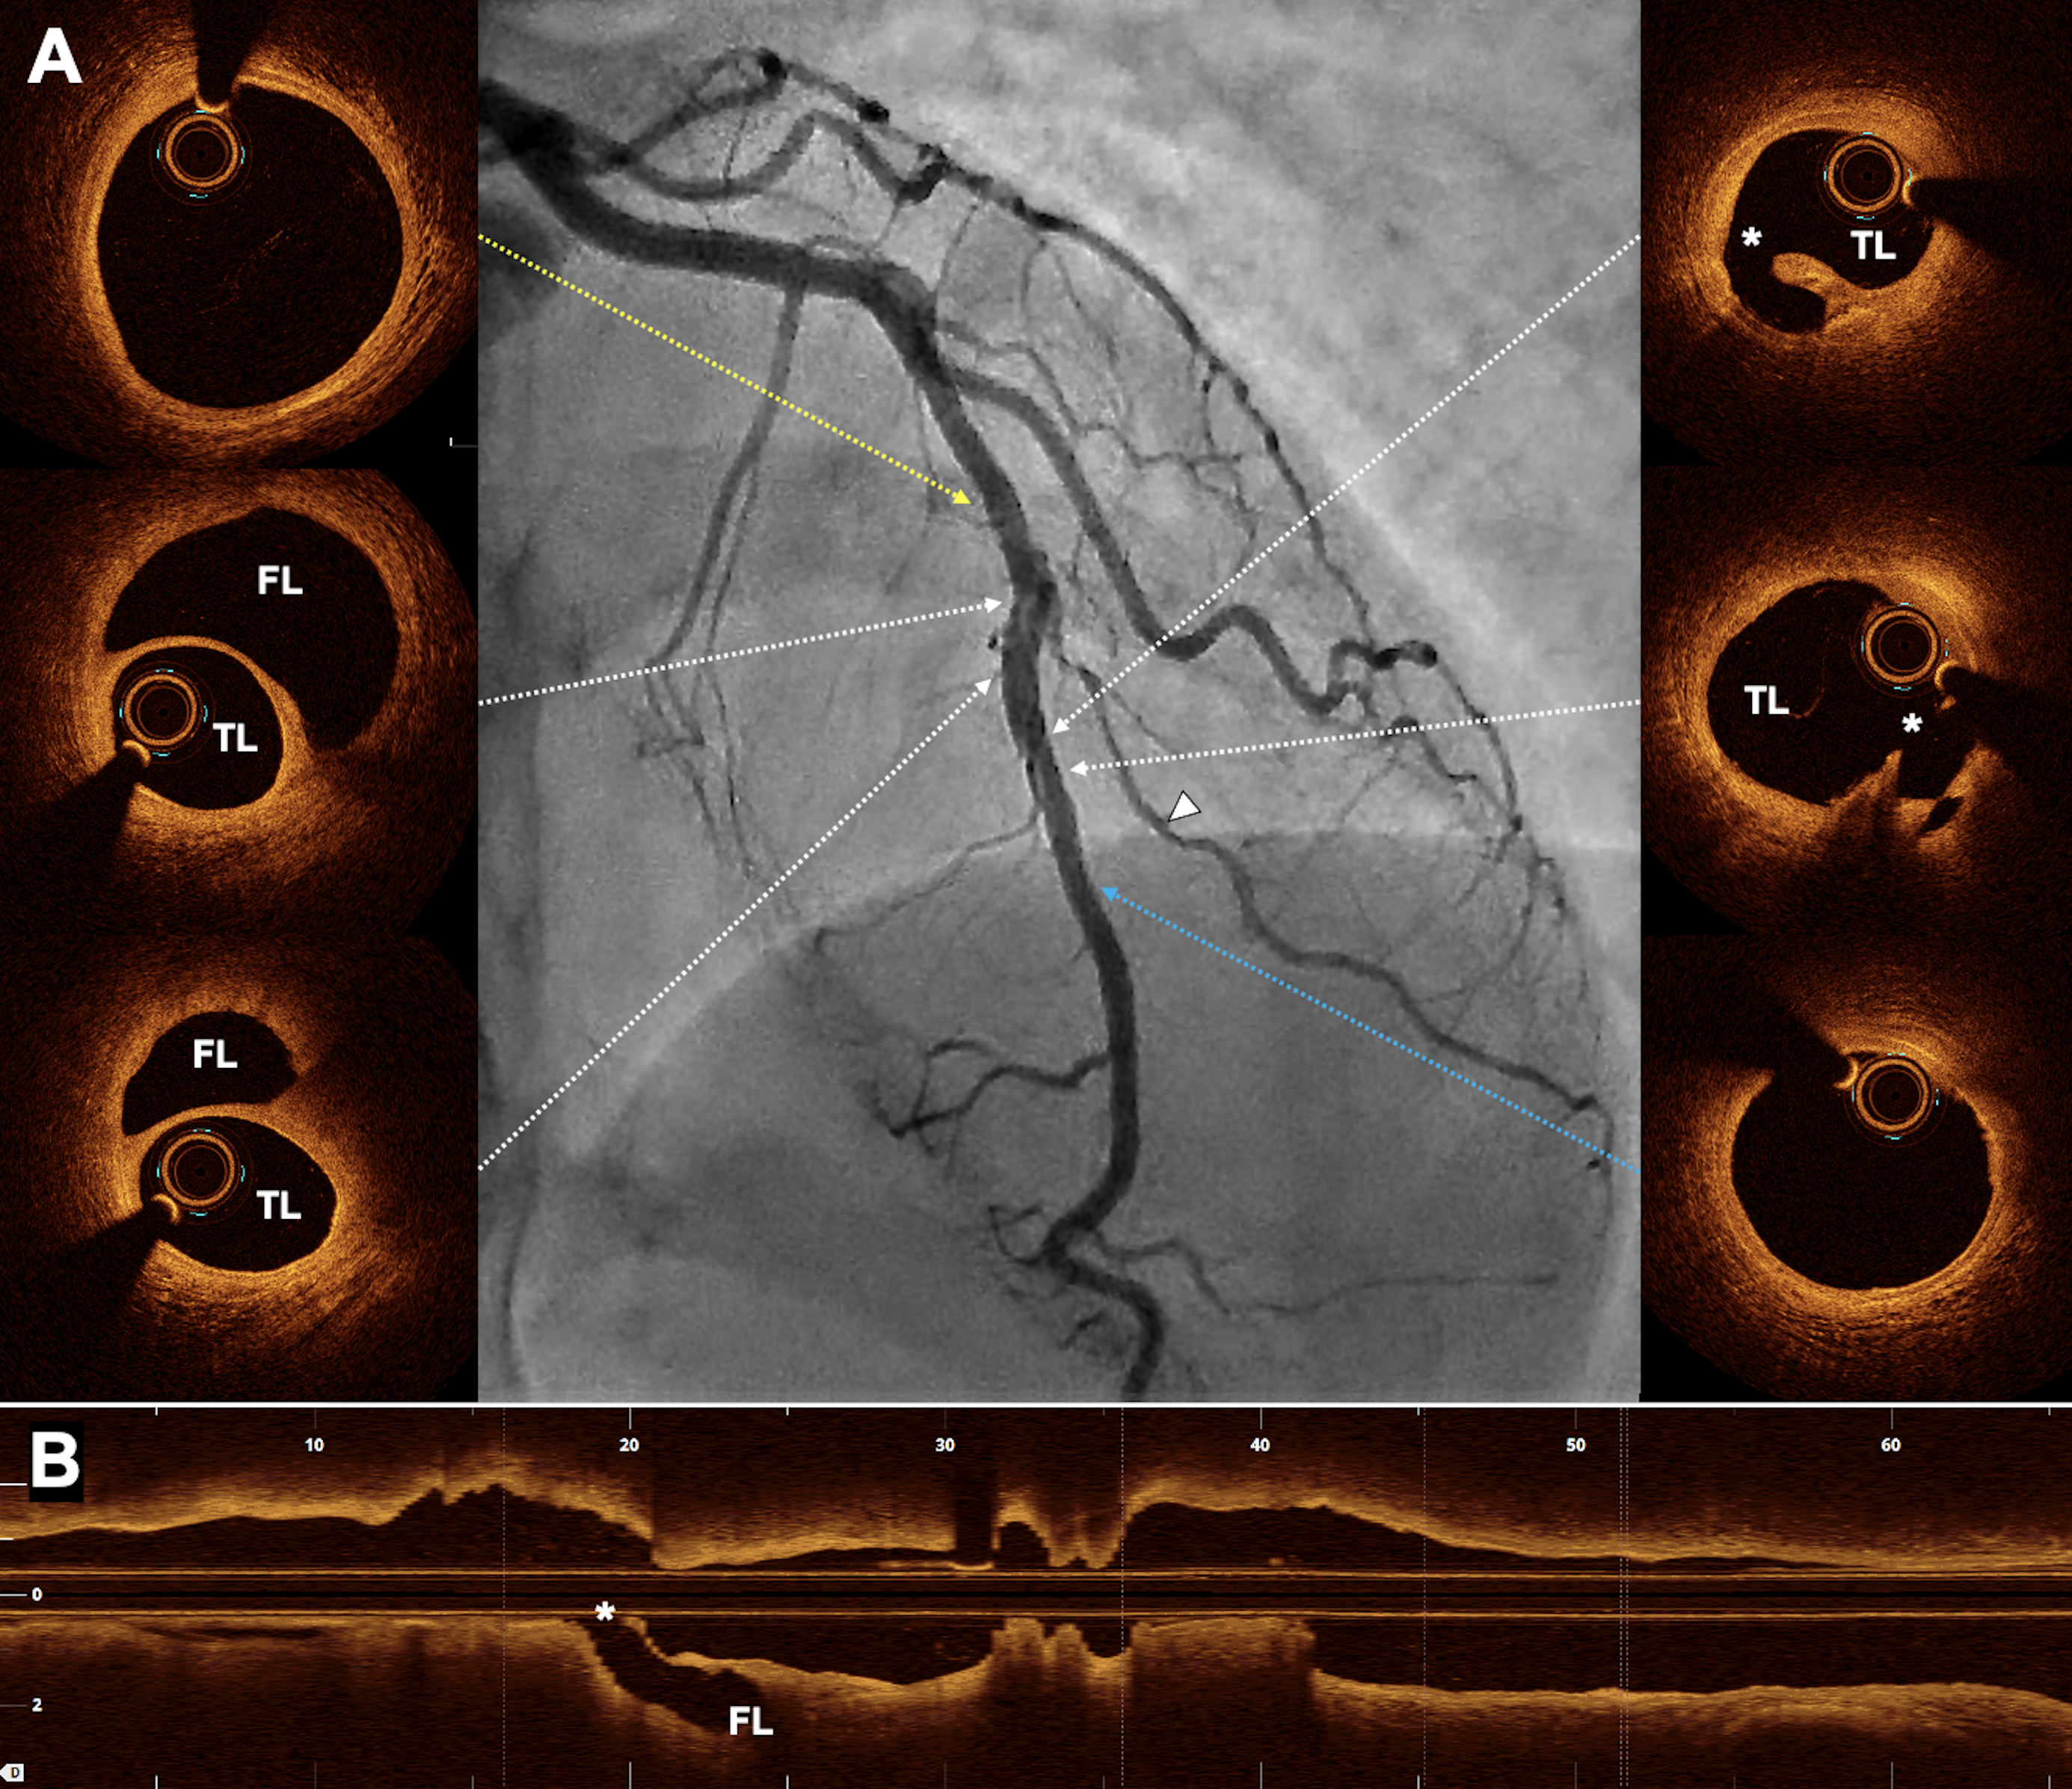

At the 1-month follow-up, repeat angiography demonstrated sustained LAD patency, with a faint radiolucent line across the previously treated segment and spontaneous healing of the diagonal branch (Figure 3; center). Optical coherence tomography revealed the intimal tear caused by the cutting balloon and the residual false lumen without compromise of flow (Figure 3). As the patient remained asymptomatic, conservative follow-up was adopted.